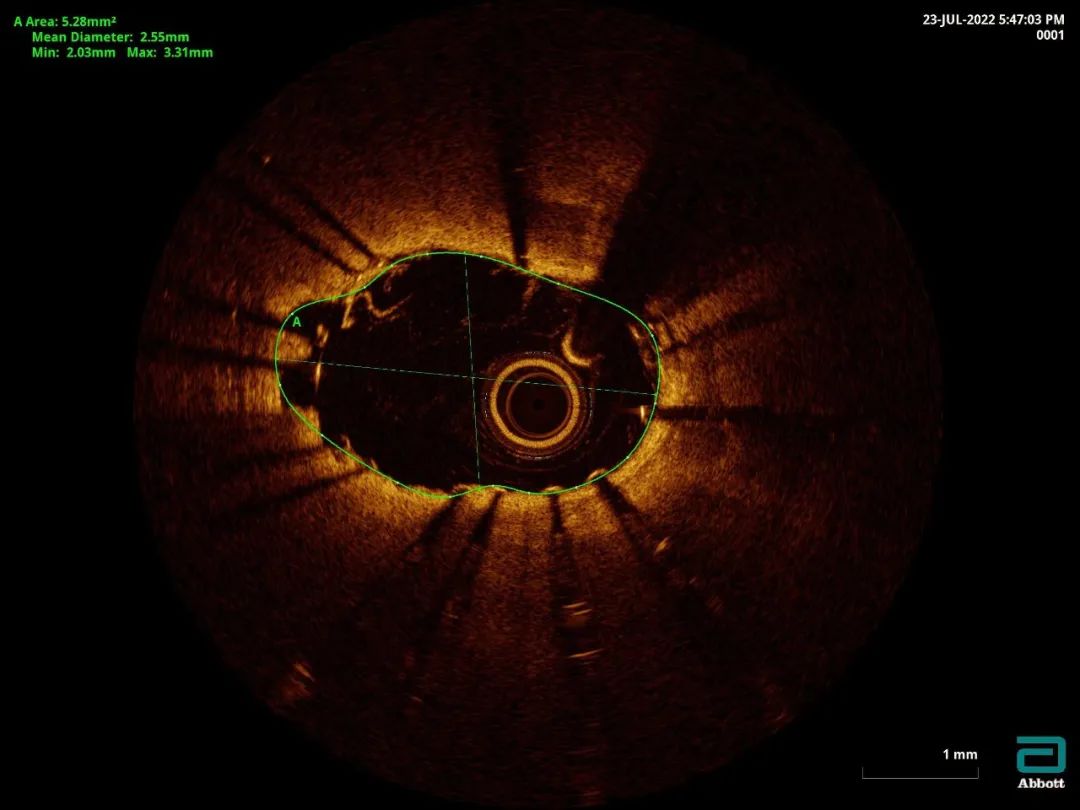

经桡动脉送入7F EBU3.5指引导管到位,Sion-blue指引导丝通过狭窄病变并送达前降支远端,1.5x15mm球囊、2.0x15mm球囊预扩之后复查造影示狭窄及血流稍改善。拟OCT评估钙化情况,但由于操作过程中患者缺血症状明显,于是决定先植入支架:前降支-左主干依次串联置入3.0x22mm及3.5x22mm Integrity支架2枚,高压后扩张呈现“狗骨头”现象,OCT提示支架膨胀不全,支架周边>180°钙化。

OCT示支架膨胀不全